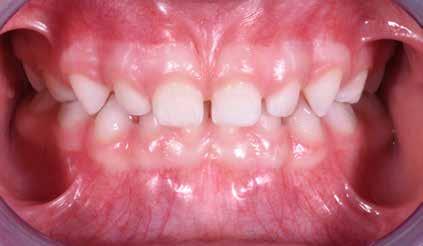

Non è sempre possibile sottoporre il paziente a queste indagini diagnostiche; per migliorare il successo e la riuscita del protocollo è necessario un approccio meticoloso ed una serie di informazioni e un’analisi dettagliata dei comportamenti per rendere il paziente collaborante, come descritto precedentemente. Questo tipo di documentazione non prevede radiografe vista la giovane età del paziente e, quindi, la diagnosi dovrà basarsi sull’esame clinico, fotografco e sull’anamnesi familiare (Snow 2005) Figg. 22-46

Il check-up ortodontico del paziente di età superiore ai sei anni

Nel caso dei pazienti di età superiore ai sei anni la documentazione precedentemente descritta sarà integrata anche con le radiografe. L’esame radiologico è assolutamente necessario ai fni della diagnosi ortognatodontica. A causa dell’età per lo più giovane dei pazienti, nella routine clinica il numero ed il tipo di radiografe dovrebbero essere stabiliti in modo da ottenere la massima quantità di informazioni con il minimo dosaggio radiologico. Le radiografe indicate per la diagnosi ortognatodontica possono essere divise in due categorie:

Fig. 15 > Immagine intraorale frontale.

Fig. 16 > Immagine intraorale laterale destra.

Fig. 17 > Immagine intraorale laterale sinistra.

Fig. 18 > Immagine occlusale superiore.

Fig. 19 > Dettaglio degli incisivi superiori.

Fig. 20 > Sorriso laterale destro.

Fig. 21 > Sorriso laterale sinistro.